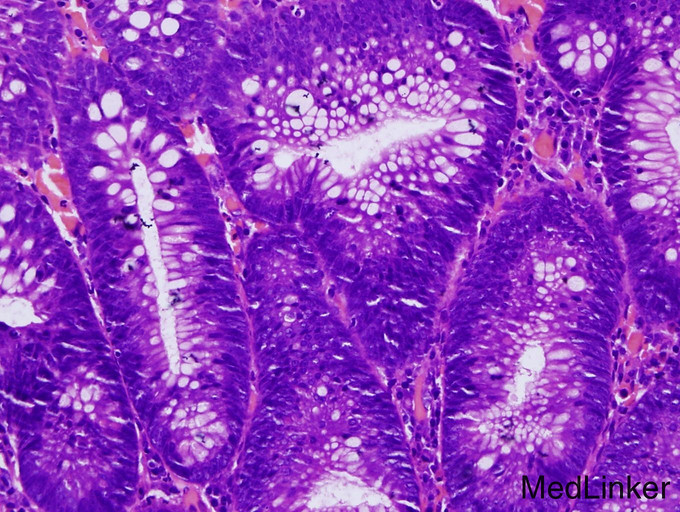

体检:体温36.5℃,脉搏72次/分,呼吸16次/分,血压124/60mmHg。发育正常,营养良好,面容正常,自主体位,步态蹒跚,神清,查体合作。实验室检查:左下腹可见一纵形陈旧性手术疤痕,腹柔软,无压痛反跳痛,未触及包块。心肺听诊无异常。专科体征:躯干以背部为主较多黑褐色丘疹,略粗糙,面部少许类似皮损。 辅助检查:血尿粪常规、肝肾功能均正常。2000年结肠增生物切除物病理学检查:腺样结构,腔侧细胞呈高柱状,胞浆淡染,周边细胞胞浆呈嗜碱性,其中可见核大浓染细胞和病理性核分裂。

Leser-Trelat症首先由Edmund Leser和Ulysse Lrelat描述,1900年Hollander首次强调Leser-Trelat症与内脏肿瘤的关系。本症可单独发生,亦可同时与肿瘤并存,故学者们将此种皮肤损害称为内脏肿瘤的标志,故长期以来,本病一直被认为是一种皮肤副肿瘤性综合征。临床上,Leser-Trelat症是指突然出现多发性脂溢性角化或原有的脂溢性角化损害突然增大、数目增多,就每个损害而言,Leser-Trelat症的脂溢性角化与一般的脂溢性角化相同,分布也相似,多数损害位于背部和胸部,其次为四肢、面、腹和腋部,但也可泛发,通常上肢多下肢,可伴有不同程度的瘙痒。 Leser-Trelat症多伴发腺癌,主要发生在食管和胃,也有合并白血症或蕈样肉芽肿的报道。本例患者依据典型的脂溢性角病皮损、结肠组织病理学变化可确诊。